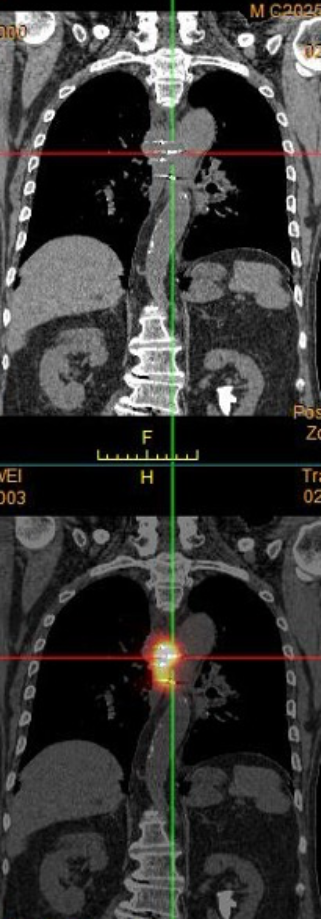

PET/CT引导下粒子植入

粒子植入的核心是精准植入有活性的或者代谢高的肿瘤区域才能起到治疗作用,我们创新性地将PET/CT引导投入粒子植入领域,建立国内首个PET/CT微创引导平台,将粒子优势与PET/CT强项有机融合。